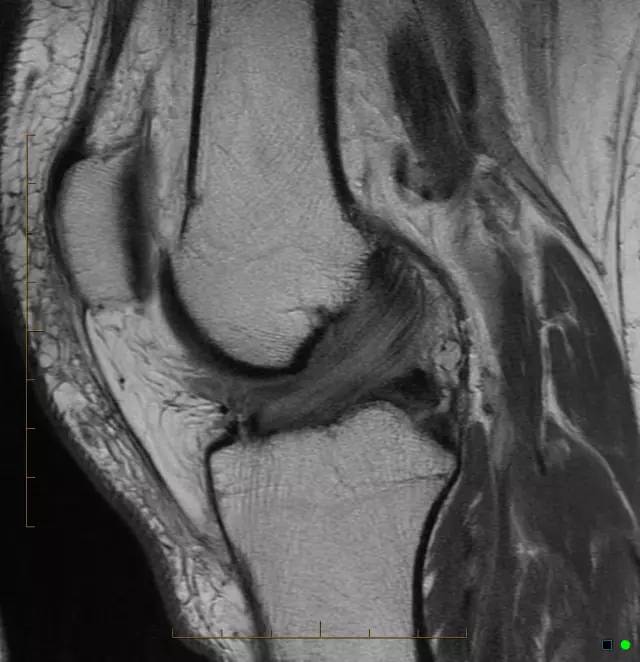

• 后交叉韧带的MR成像

后交叉韧带的MR成像

• 前交叉韧带的MR成像

前交叉韧带的MR成像